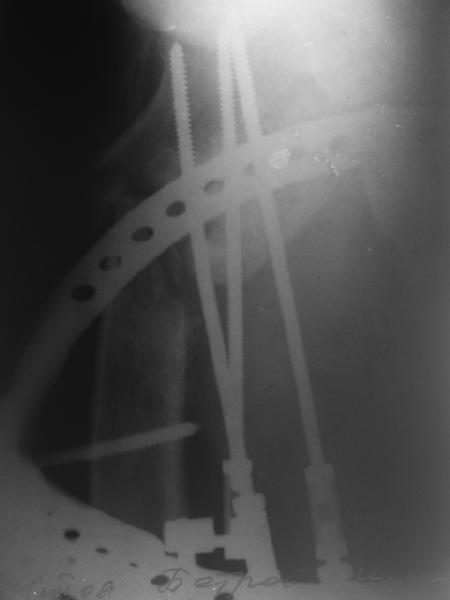

Leonid Solomin 03 Март 2009, 22:07

Уважаемый Попов Виктор!

Возможно, пример (в приложении) поможет Вам определиться с выбором тактики лечения (у нашего пациента, кроме тугого ложного сустава вертельной области, сложная деформация н/3 бедренной кости; т.к. это не имеет значения к обсуждаемой теме - оставил "за кадром"). Как Вы видите, мы в данном случае не вводили чрескостные элементы в зону установки имплантата. При отказе от наложения опоры на таз (кстати, она не обязательно может быть громоздкая спицевая; арки со стержнями-шурупами, введенными в крыло подвздошной вполне достаточно) "не удивляйтесь", если опора со стержнями-шурупами, введенными в вертельной области в скором времени дестабилизируется, возникнет воспаление мягких тканей у чрескостных элементов. Такая опора "имеет на это право": нагрузка конечности от вершины дистального фрагмента до кончиков пальцев ляжет на нее. А двух-трех введенных рядом стержней-шурупов, как их не разноси от фронтальной плоскости, в данном

случае явно недостаточно для адекватной фиксации. + для того, чтобы выбрать оптимальные чрескостные элементы для промежуточной и дистальной опор, можете воспользоваться атласом

В приложении пример пациента, близкого по картине к тому, что представил Виктор (варус и смещение периферического отломка на поперечник кзади). Сделали как раз то, что Виктор исходно намеревался - аппаратная коррекция и затем гамма.